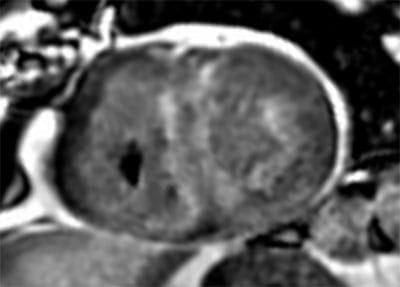

• High volume program with daily case averages of 10 CMR studies and 25-35 cardiac CTAs (50% coronary CTA, 30% structural, 20% other). Broad case complexity, including CAD, structural heart pathologies, congenital heart disease,  and implantable devices. Routine use of cutting edge technology, including T1/ECV mapping, quantitative perfusion, free-breathing CMR exam, artificial intelligence based CT analyses, CT-FFR, structural planning and simulation.